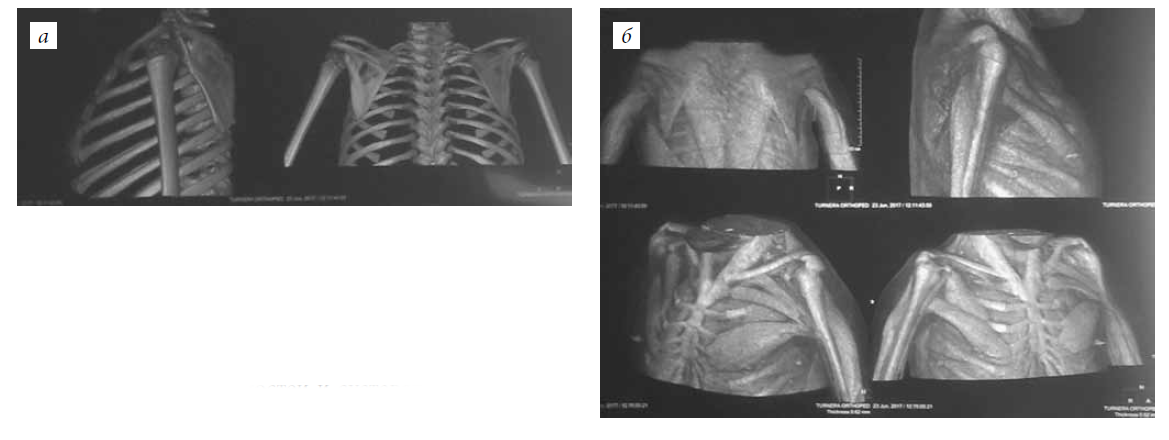

The patients were examined preoperatively and ≥1 year after the intervention. The following indicators were examined in a clinical examination: the amplitude of movements in the elbow joint (active and passive), the strength of the flexor muscles of the forearm and the donor area, and the ability to perform daily activities independently. The amplitude of elbow joint movements was determined using a goniometer. Muscle strength was evaluated on a six-point scale (0–5 points) when moving on a plane, while overcoming gravity, and with manual resistance. BMB was examined via palpation in the position of adduction, extension, and internal rotation of the shoulder. When surgery was planned for children >4 years of age, electromyography (EMG) of the muscles of the flexors and extensors of the forearm and the broadest muscle of the back was performed. Due to the complexity of the neurophysiological study and magnetic resonance imaging in young children, a computed tomography examination of the chest and shoulder in different modes was performed to assess the condition of the muscles of potential donor areas; this enabled a simultaneous understanding regarding the state of soft tissues, bones, and joints of the segment under study (Fig. 1).

Fig. 1. CT scan of the chest and shoulder in different modes for the simultaneous visualization of the soft tissues, bones, and joints of the segment under study: a — visualization of the bones and the joints; b — visualization of the muscles of the shoulder and the chest